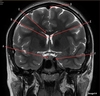

Image weighting and axis

T1 Sagittal

A

Lateral Ventricle

B

Corpus Callosum

C

Thalamus

D

Tentorium

E

4th Ventricle

F

Medulla Oblongata